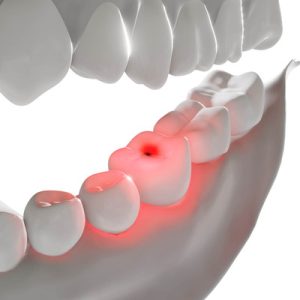

Tooth sensitivity is a condition experienced by millions of Americans…